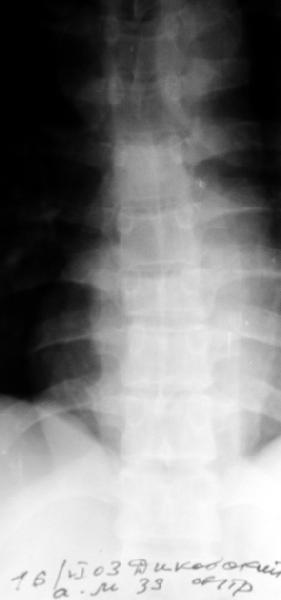

Перелом IX грудного позвонка

Мужчина 39 лет, перевернулся в машине 12 июня. Клинически неврологии нет. Нужна ли репозиция и оперативная фиксация этого повреждения? Если нет, то как вести? Спасибо заранее.Алексей Рунков, УНИИТО

Agreed, except that loss of posterior vertebral body height on the lateral radiograph suggests middle column involvement as well, and therefore a diagnosis of burst fracture. This is confirmed on the AP by (albeit subtle) widening of the pedicles at the level of injury. In keeping with this diagnosis, the lateral also suggests retropulsion of fracture fragments into the canal. I concur that unless there is associated facet subluxation or interspinous widening on CT (possible, but unlikely given the well-maintained alignment and given that on the AP radiograph the spinous processes seem reasonably equidistant) this is a stable burst fracture that I would treat with a TLSO for 3 months.

A CT would be helpful to determine if there is middle column involvement. Also it would help determine if the posterior interspinous ligament is intact (lack of interspinous widening. The available images appear to show an anterior column only injury. If other imaging tests confirm this combined with normal neurological function nonoperative treatment with a hyperextension brace or nothing is appropriate.